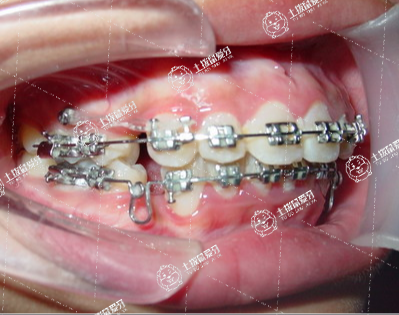

牙列擁擠輕度者可以直接帶上牙套進行排齊,如果擁擠嚴重,可能需要拔牙治療,如果擁擠程度較輕,簡單的排齊會有輕微的突出,就需要對前牙的鄰面進行去釉處理,就是前牙稍微磨掉一點排齊。如果不想磨牙,又沒有智齒或智齒要拔掉,把牙齒往后推,空出間隙和前牙排齊即可。

牙齒擁擠矯正通常需要一年或者兩年的時間。每個人牙齒的情況都不太一樣,所以牙齒矯正需要的時間也不一樣,具體時間還需要到專業(yè)牙科就診檢查之后才能確定。牙齒矯正的材料和方式有很多,例如功能托槽、活動托槽、固定托槽等,可以根據(jù)自己的實際情況來選擇合適的材料和治療方案。在進行牙齒矯正時,不要吃太甜的食物,避免齲齒的出現(xiàn)。

如果是輕度的牙列擁擠,這種情況不需要拔牙,可以采用固定矯正或隱形矯正的方法來進行治療,這種情況下需要的時間比較短,可能需要一年就可以了。但是如果是重度的牙列擁擠,嚴重的時候還需要拔牙,這樣才能夠進行矯正,這種情況需要的時間可能會長一些,可能需要兩年到三年。另外牙列擁擠矯正時間還和患者的年齡有關,一般兒童矯正的時間會短,但是如果是成年人,矯正的時間會長一些。